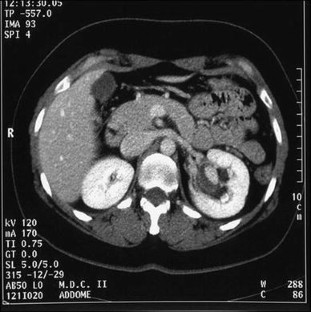

A 40-year-old woman was referred to our department for further investigation of a renal mass identified at an ultrasound (US) examination carried out in a private clinic because of abdominal pain. The mass was oval and hypoechoic, measured about 20 mm in diameter and was located near the left renal sinus; color Doppler showed peripheral blood flow. US examination carried out in our department using different equipment confirmed the presence of the mass but revealed intralesional blood flow suggesting aneurysm. This diagnosis was confirmed at subsequent computed tomography (CT) scanning and magnetic resonance imaging (MRI). The patient refused to undergo surgery and she is currently being monitored and has suffered no sequelae.

Fig. 4